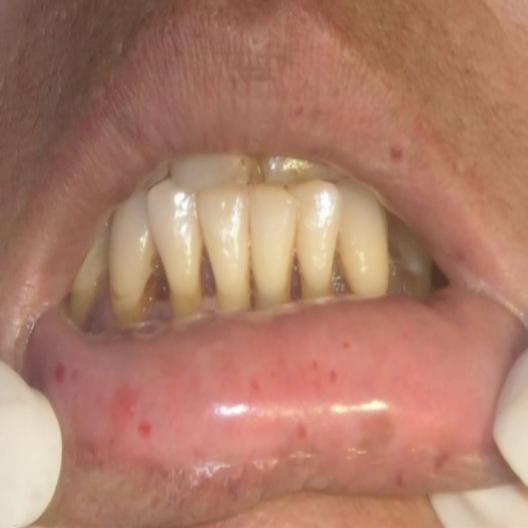

A clinical guide to oral manifestations and diagnosis of limited systemic sclerosis: a case report

Rare angiofibrolipoma of the oral cavity: a case report